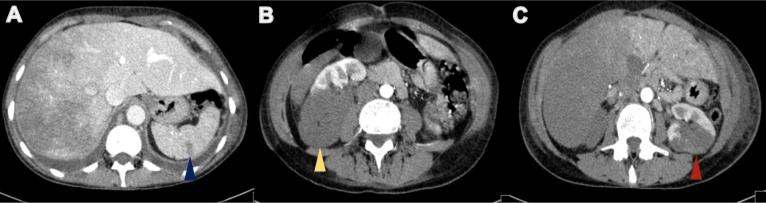

Arterial thrombosis and Budd-Chiari syndrome are rare conditions in lung cancer patients. We report the case of a 53-year-old woman who presented with respiratory symptoms, lumbar pain, weight and appetite loss, and an x-ray showing a lung nodule and diffuse micro-opacities. She was diagnosed with lung neoplasia with extensive lung, liver, lymph node and bone metastases. After discharge she was readmitted with a respiratory infection, and as her condition deteriorated, computed tomography was performed and revealed ischaemic areas in the spleen and kidney, and venous thrombosis, related to Budd-Chiari syndrome, with hepatic ischaemia. Despite hypocoagulation, her clinical condition deteriorated and she died soon afterwards.

动脉血栓形成和布加综合征在肺癌患者中是罕见病症。我们报告一例53岁女性病例,该患者出现呼吸道症状、腰痛、体重减轻和食欲减退,X线显示肺部有结节及弥漫性微阴影。她被诊断为患有肺肿瘤,伴有广泛的肺、肝、淋巴结和骨转移。出院后,她因呼吸道感染再次入院,随着病情恶化,进行了计算机断层扫描,结果显示脾脏和肾脏有缺血区域,以及与布加综合征相关的静脉血栓形成和肝缺血。尽管存在低凝状态,但她的临床状况仍恶化,不久后死亡。